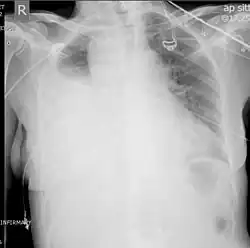

| Chest X-ray showing left sided hemothorax (arrowed) | |

Chest X-ray

A chest X-ray is the most common technique used to diagnosis a hemothorax.[23] X-rays should ideally be taken in an upright position (an erect chest X-ray), but may be performed with the person lying on their back (supine) if an erect chest X-ray is not feasible. On an erect chest X-ray, a hemothorax is suggested by blunting of the costophrenic angle or partial or complete opacification of the affected half of the thorax. On a supine film the blood tends to layer in the pleural space, but can be appreciated as a haziness of one half of the thorax relative to the other.[5] A small hemothorax may be missed on a chest X-ray as several hundred milliliters of blood can be hidden by the diaphragm and abdominal viscera on an erect film. Supine X-rays are even less sensitive and as much as one liter of blood can be missed on a supine film.[24]